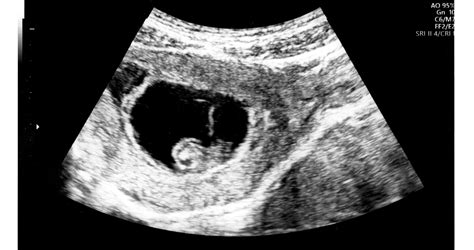

Korábbi tanulmányok alapján már lehetett arra következtetni, hogy a várandós nő étrendje hatással lehet arra, hogy a gyerek később milyen ételeket kedvel. Az északkelet-angliai Durham Egyetemen most közvetlenül azt vizsgálták, hogy magzatok pár héttel a születésük előtt hogyan reagálnak a különböző ízekre. A Psychological Science című tudományos folyóiratban közölt tanulmányban a kutatók felhívták a figyelmet, hogy a magzatvízbe átszivárognak az ízek az anya által fogyasztott ételekből. Ízeket már egy 14 hetes magzat ízlelőbimbói is észlelhetnek, illatokat pedig nagyjából a 24. hét környékén. A kutatók ultrahangfelvételek alapján próbálták eldönteni, hogy a magzatok vajon különbséget tudnak-e tenni a különféle ízek között. Két csoportra osztottak 70 várandós kismamát, az egyik tagjait arra kérték, 20 perccel az ultrahangvizsgálat előtt vegyenek be egy porított kelkáposztát tartalmazó kapszulát, a másik csoportnak pedig sárgarépa-kapszulát adtak. Az ultrahangon a magzatok arckifejezését vizsgálták a terhesség 32. vagy 36. hetében. Azt fedezték fel, hogy a keserű kelkáposztás ízre reagálva kétszer olyan gyakran fordult elő sírásra hasonlító grimasz, mint a sárgarépás vagy a semleges ízre.